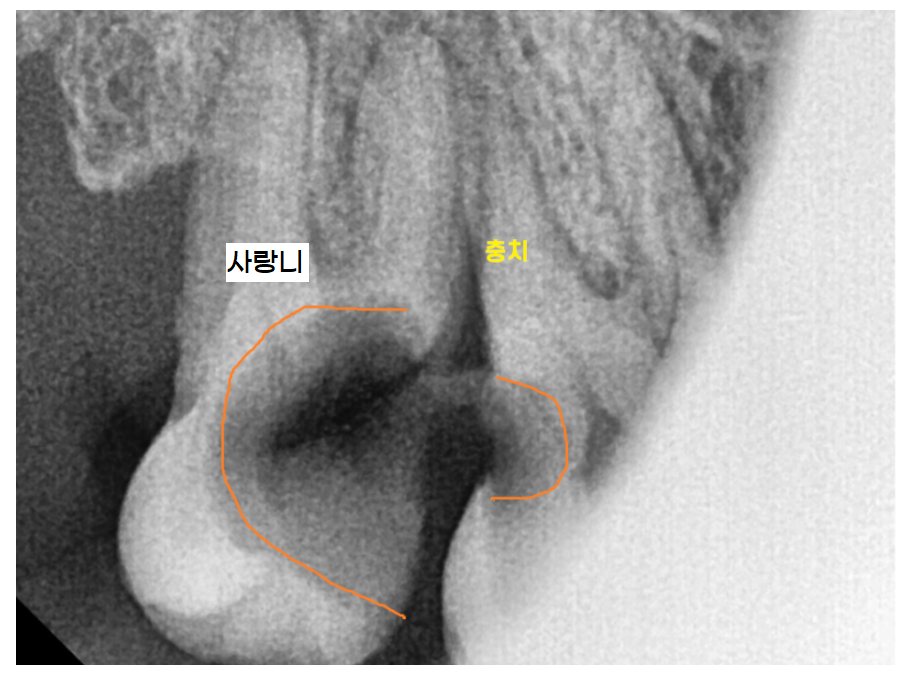

사랑니로 인해 2차 충치나 잇몸 질환이 생길 가능성이 높으면

뽑는 것을 추천드려요~

240731 사랑니로 인해 앞에 치아까지 충치가 생겼어요ㅠㅠ